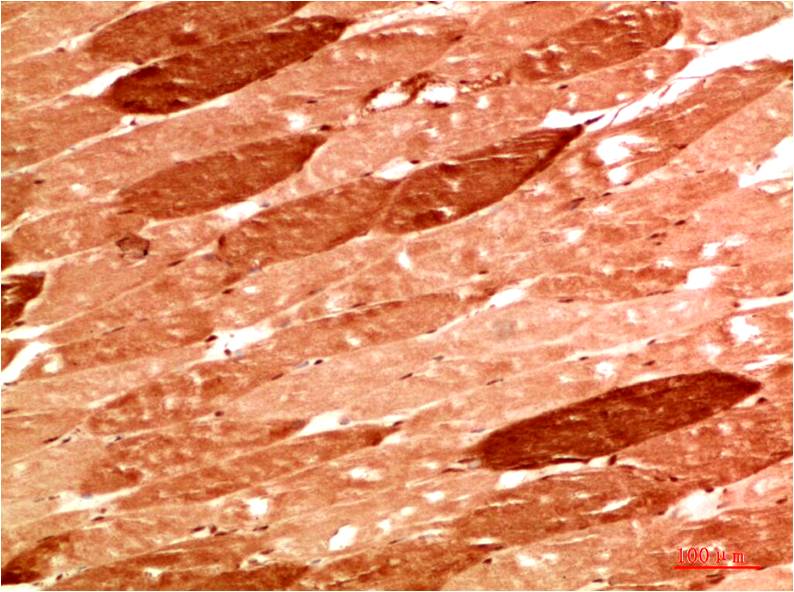

Acetyl P53(K382) Mouse Monoclonal Antibody(5H10)

Applications :IHC

| Recommended dilutions: | IHC: 1:100-200 |

| Specificity: | The Acetyl P53(K382) Mouse Monoclonal Antibody can detects endogenous Acetyl P53(K382) proteins. |